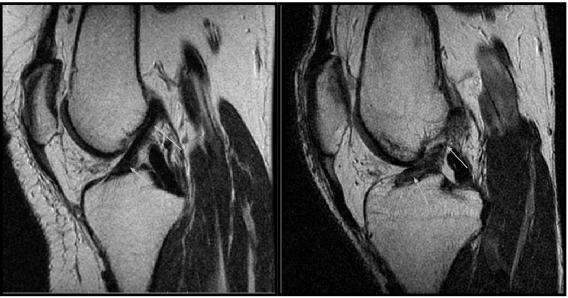

What is seen in this image

A

• slight tear in lateral horn of posterior meniscus

• no contrast required for MRI

What is happening in these images

normal vs torn ACL